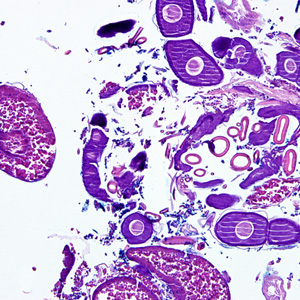

Case #275 – May, 2010

A 70-year-old female, who had recently returned from a trip to Madagascar, went to the hospital for a painful sensation on the underside of her left foot while walking. Examination of the area between the hallux and index toes revealed an ulcerative lesion. A biopsy was performed and sent to the Pathology Department for work-up. The specimen was sectioned, stained with hematoxylin and eosin (H&E) and examined by the attending pathologist. Figures A and B show what was observed at 40x magnification. Figures C and D show the same fields at 200x magnification, respectively. What is your diagnosis? Based on what criteria?

Figure B